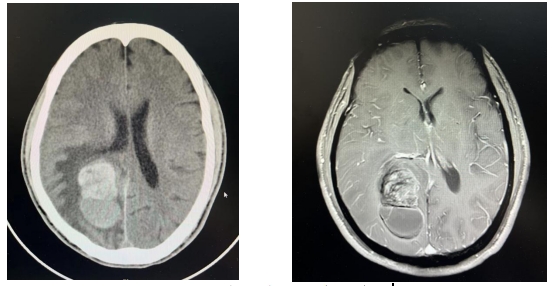

为进一步明确病变性质,神经外科的医生进行了更为详细的检查,颅脑增强MR结果提示:不排除转移瘤可能。也就是头颅内的肿瘤是别的地方转移过来的。

左下角异常部分为肿瘤

考虑到他5年前左手指曾行“黑色素瘤切除术”,专家们一直认为,张叔颅内病变高度怀疑为恶性黑色素瘤转移灶,目前肿瘤伴有出血,同时已经对周围脑组织形成了压迫,手术切除指征非常明确,需要手术。